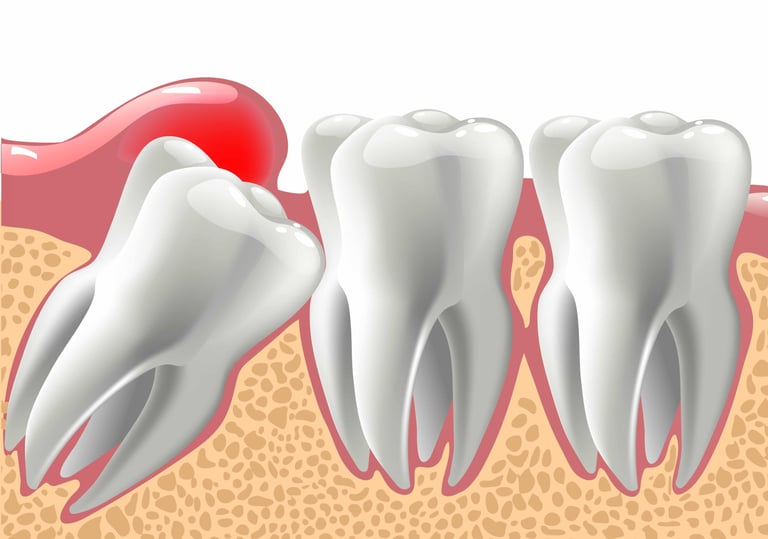

Pain caused by a wisdom tooth can sometimes be hard to identify, especially before it comes through the gums. It is often described as a dull pain or pressure in the back of the jaw and can sometimes be accompanied by headaches. This pain and discomfort are normal – in the sense that many people experience it – but that does not mean that it should be ignored.

3. Everyone Will Need All Four Wisdom Teeth Removed

If they cause pain and become impacted even if they don’t come up through the gums; sometimes they can grow in sideways and hit the roots of the neighboring molars or shift things around in the jawbone itself. In cases like this, they would still need to be removed, even if they aren’t visible.